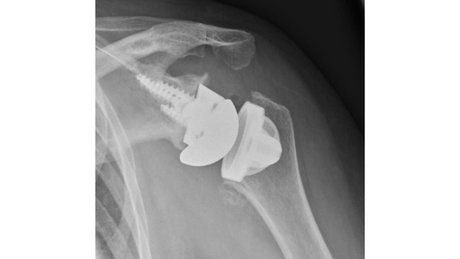

Therapieoption: Implantation einer anatomischen/inversen Schulterprothese

Die Implantation einer Schulterprothese kann bei Arthrose im Schultergelenk, der sogenannten Omarthrose, nötig werden. Hierbei kann man zwei verschiedenen Formen der Arthrose unterscheiden:

In einem Fall ist die Rotatorenmanschette, also die umgebenden Sehnen an der Schulter, welche die Stabilität und Beweglichkeit des Gelenkes gewährleisten, intakt. Der Knorpel ist jedoch aufgebraucht. Bei der Implantation einer Prothese werden die Gelenkpartner ersetzt und deren Form wird beibehalten. Eine sogenannte anatomische Schulterprothese wird implantiert.

Sollte die Rotatorenmanschette, also die umgebenden Sehnen an der Schulter, welche die Stabilität und Beweglichkeit des Gelenkes gewährleisten, nicht mehr intakt sein, dann ist ein anderer Prothesentyp nötig. Hierbei ist die Prothese so aufgebaut, dass sie durch Umkehr der Gelenkformen, die Funktion der fehlenden Sehnen übernimmt. Die flache Pfanne wird sphärisch und der ursprünglich runde Kopf wird als Schale implantiert. Dadurch kann man trotz fehlender Rotatorenmanschette die nötige Stabilität und Beweglichkeit des Schultergelenkes wiederherstellen. Eine sogenannte inverse Schulterprothese wird implantiert.

Sollte bei Ihnen eine Prothesenimplantation durchgeführt werden, sind unter Umständen zuvor verschiedenen bildgebende Verfahren nötig um die korrekte Prothese auswählen zu können.

Bei allen Prothesenformen gibt es verschiedenen Designs. Insgesamt versucht man so knochensparend wie möglich zu operieren. Das bedeutet viel vom eigenen Knochen zu erhalten. Schaftlose Prothesen und kurze Schäfte werden daher bevorzugt. Bei vorbestehender eingeschränkter Knochenqualität kann zur Aufrechterhaltung der Stabilität eine etwas längere Verankerung im Knochen notwendig sein.

Insgesamt ist wichtig, dass man individuell entscheiden muss ob eine Prothese implantiert wird und welche Form der Prothese gewählt wird.

Üblicherweise schließt sich an die Operation eine 5-6 wöchige Nachbehandlung ohne Kraftaufwendung am Arm an. Im Anschluss ist die Prothese gut eingeheilt und man kann mit einer Belastungssteigerung starten. Dies erfolgt üblicherweise im Rahmen eine Rehabilitation, welche bei der Festlegung des Operationstermins, vorab reserviert werden kann.

Auch Revision einer vorhandenen Schulterprothese, die Konversion von anatomischer Prothese auf eine inverse Prothese, partieller Wechsel oder gesamter Wechsel werden angeboten und durchgeführt.